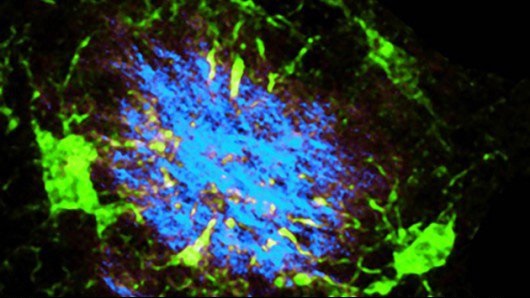

تحقیقات قبلی نشان داده بودند، متغیرهای پروتئین مزبور با بیماریهای عصبی مانند جنون، آلزایمر، پارکینسون و بیماری اسکلروز جانبی آمیوتروفیک (ALS) مرتبط هستند. این پروتئین که در سلولهای مغزی موسوم میکروگلیا یافت میشود، مسؤولیت نگهداری و ترمیم سیستم عصبی مرکزی بدن را بر عهده دارد.

در تحقیق دوم، دانشمندان نقش TREM2 را در بروز اماس بررسی کردند. تصور میشود یکی از مولفههای دخیل در این بیماری، حمله سلولهای ایمنی است که به اشتباه، لایه محافظتی سلولهای عصبی موسوم به میلین را هدف قرار میدهند. در این فرآیند، بقایای میلین در بافت مغزی باقی میماند، اثرات بیماری اماس را افزایش داده و به توانایی مغز برای ترمیم خود آسیب میزند.